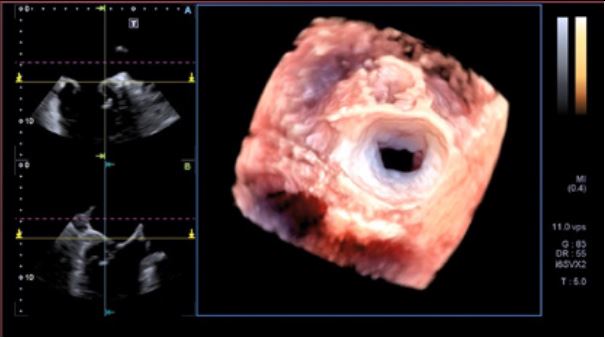

Аналіз мітрального клапана в 4D (4D MVA)

Цей унікальний інструмент забезпечує анатомічну та функціональну оцінку мітрального клапана, проводячи близько 40 вимірювань за 30 секунд, та допомогає лікарю при плануванні інтервенційного втручання, наприклад для операції транскатетерної імплантації мітрального клапана.

Діагностика виконується за допомогою трансезофагеального 4D датчика PEI-512VX.

- Інтуїтивно-зрозумілий кольоровий 3D аналіз

- 4-віконний дисплей (обрані користувачем зрізи, різні площини сканування, 3D-реконструкція)